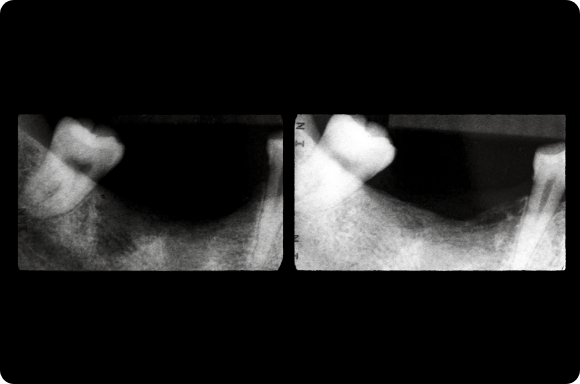

This mastery-level course discusses both the prevention and management of surgical and restorative complications. Within the surgical realm, the presentation focuses on early implant failure and later peri-implant disease. Prosthetic concepts will involve preventative prosthesis design, screw/abutment removal, and sequencing that acknowledges the importance of patient experience.

The implant curriculum is an interactive, procedure-based series of courses that use individual cases to teach current implant treatment. This approach is in contrast to conventional dental education that focuses more on didactic topics and theory. The purpose of using this educational approach is to highlight the patients and procedures found in everyday clinical practice, where the most important concepts are observed and discussed in multiple clinical scenarios.